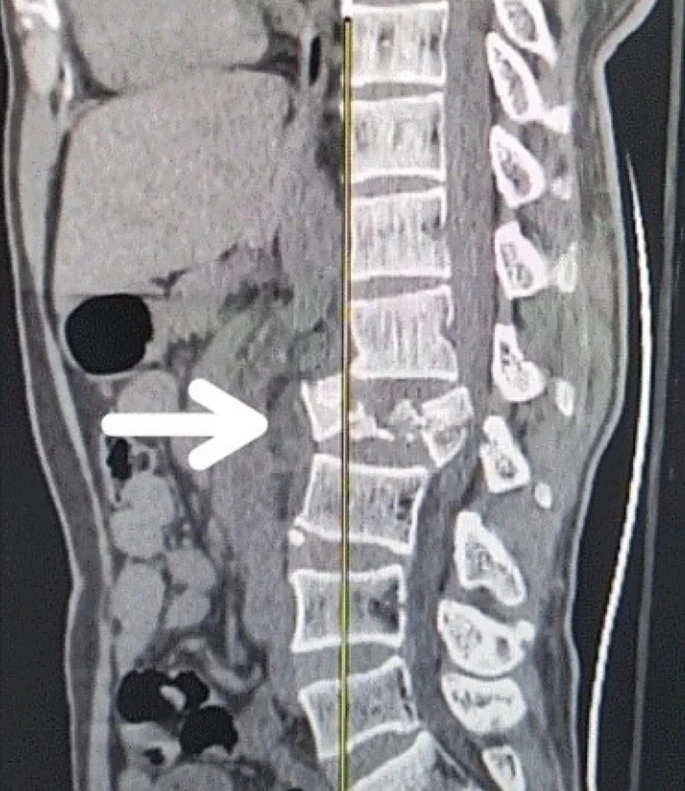

創(chuàng)傷性脊髓損傷是由于脊柱受到突然的強(qiáng)力撞擊,導(dǎo)致椎骨骨折、脫臼、擠壓或壓縮(圖1)。主要原因包括機(jī)動(dòng)車(chē)事故,其中汽車(chē)和摩托車(chē)碰撞占每年新增脊髓損傷病例的近一半。跌倒,尤其是65歲及以上人群的跌倒,是造成脊髓損傷的重要原因,約占60%。體育活動(dòng),例如沖擊性運(yùn)動(dòng)和淺水潛水,約占此類損傷的10%。

圖1:X射線圖像顯示脊髓損傷,椎骨骨折和移位,如白色箭頭所示